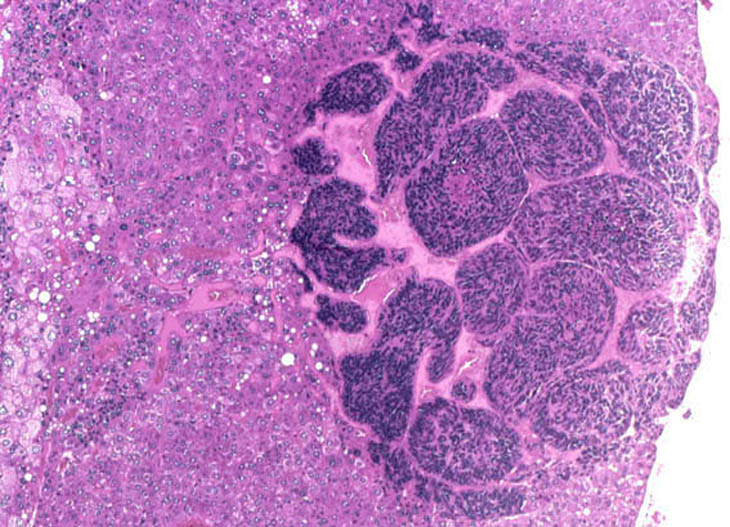

A basophilic hepatoblastoma is arising within a discrete hepatocellular adenoma.